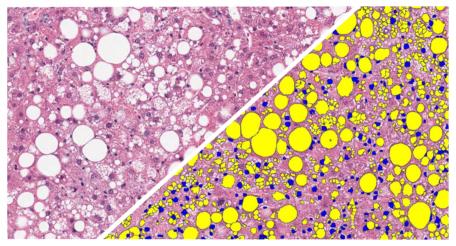

Quantify the area, diameter, perimeter, and number of white spaces per region of interest in brightfield images. Ideally suited for analysis of lipids in brown and white adipose tissue, lipid droplets in liver tissue (steatosis), and alveoli area in lung.